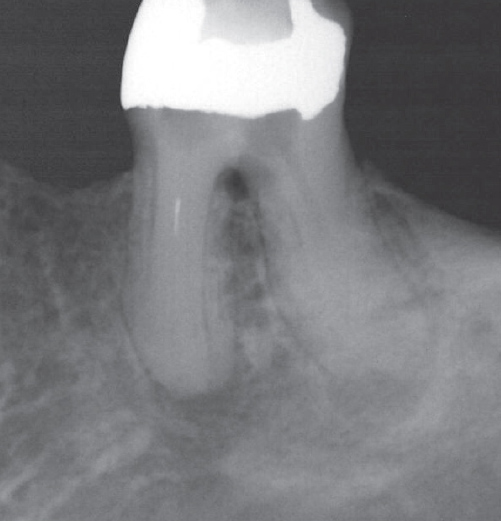

Before

Before Root Canal treatment